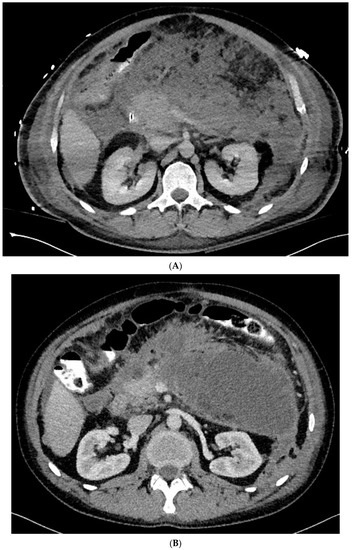

Figure 1. (A–L) Endoscopic treatment of walled-off pancreatic necrosis. In the second week of acute necrotizing pancreatitis, the acute necrotic collection (A) is visible in the abdominal contrast-enhanced computed tomography (CECT), which evolved in the sixth week of the illness duration into the symptomatic walled-off pancreatic necrosis (B). Patient qualified for endoscopic treatment (C–F) transmural drainage using the self-expanding metal stent (C,D) and endoscopic necrosectomy (E,F) was performed. In the second week of endotherapy, the endoscopic retrograde pancreatography (G–J) was performed. During pancreatography, the complete pancreatic duct disruption was stated (G–I) and transpapillary drainage was carried out (J). After achieving the treatment’s success and the complete regression of the necrotic collection, the transpapillary stent was observed in the bottom of the collection via the endoscopic view from the stomach’s side through the transmural stent (K). Control CECT confirmed the total regression of the collection (L).